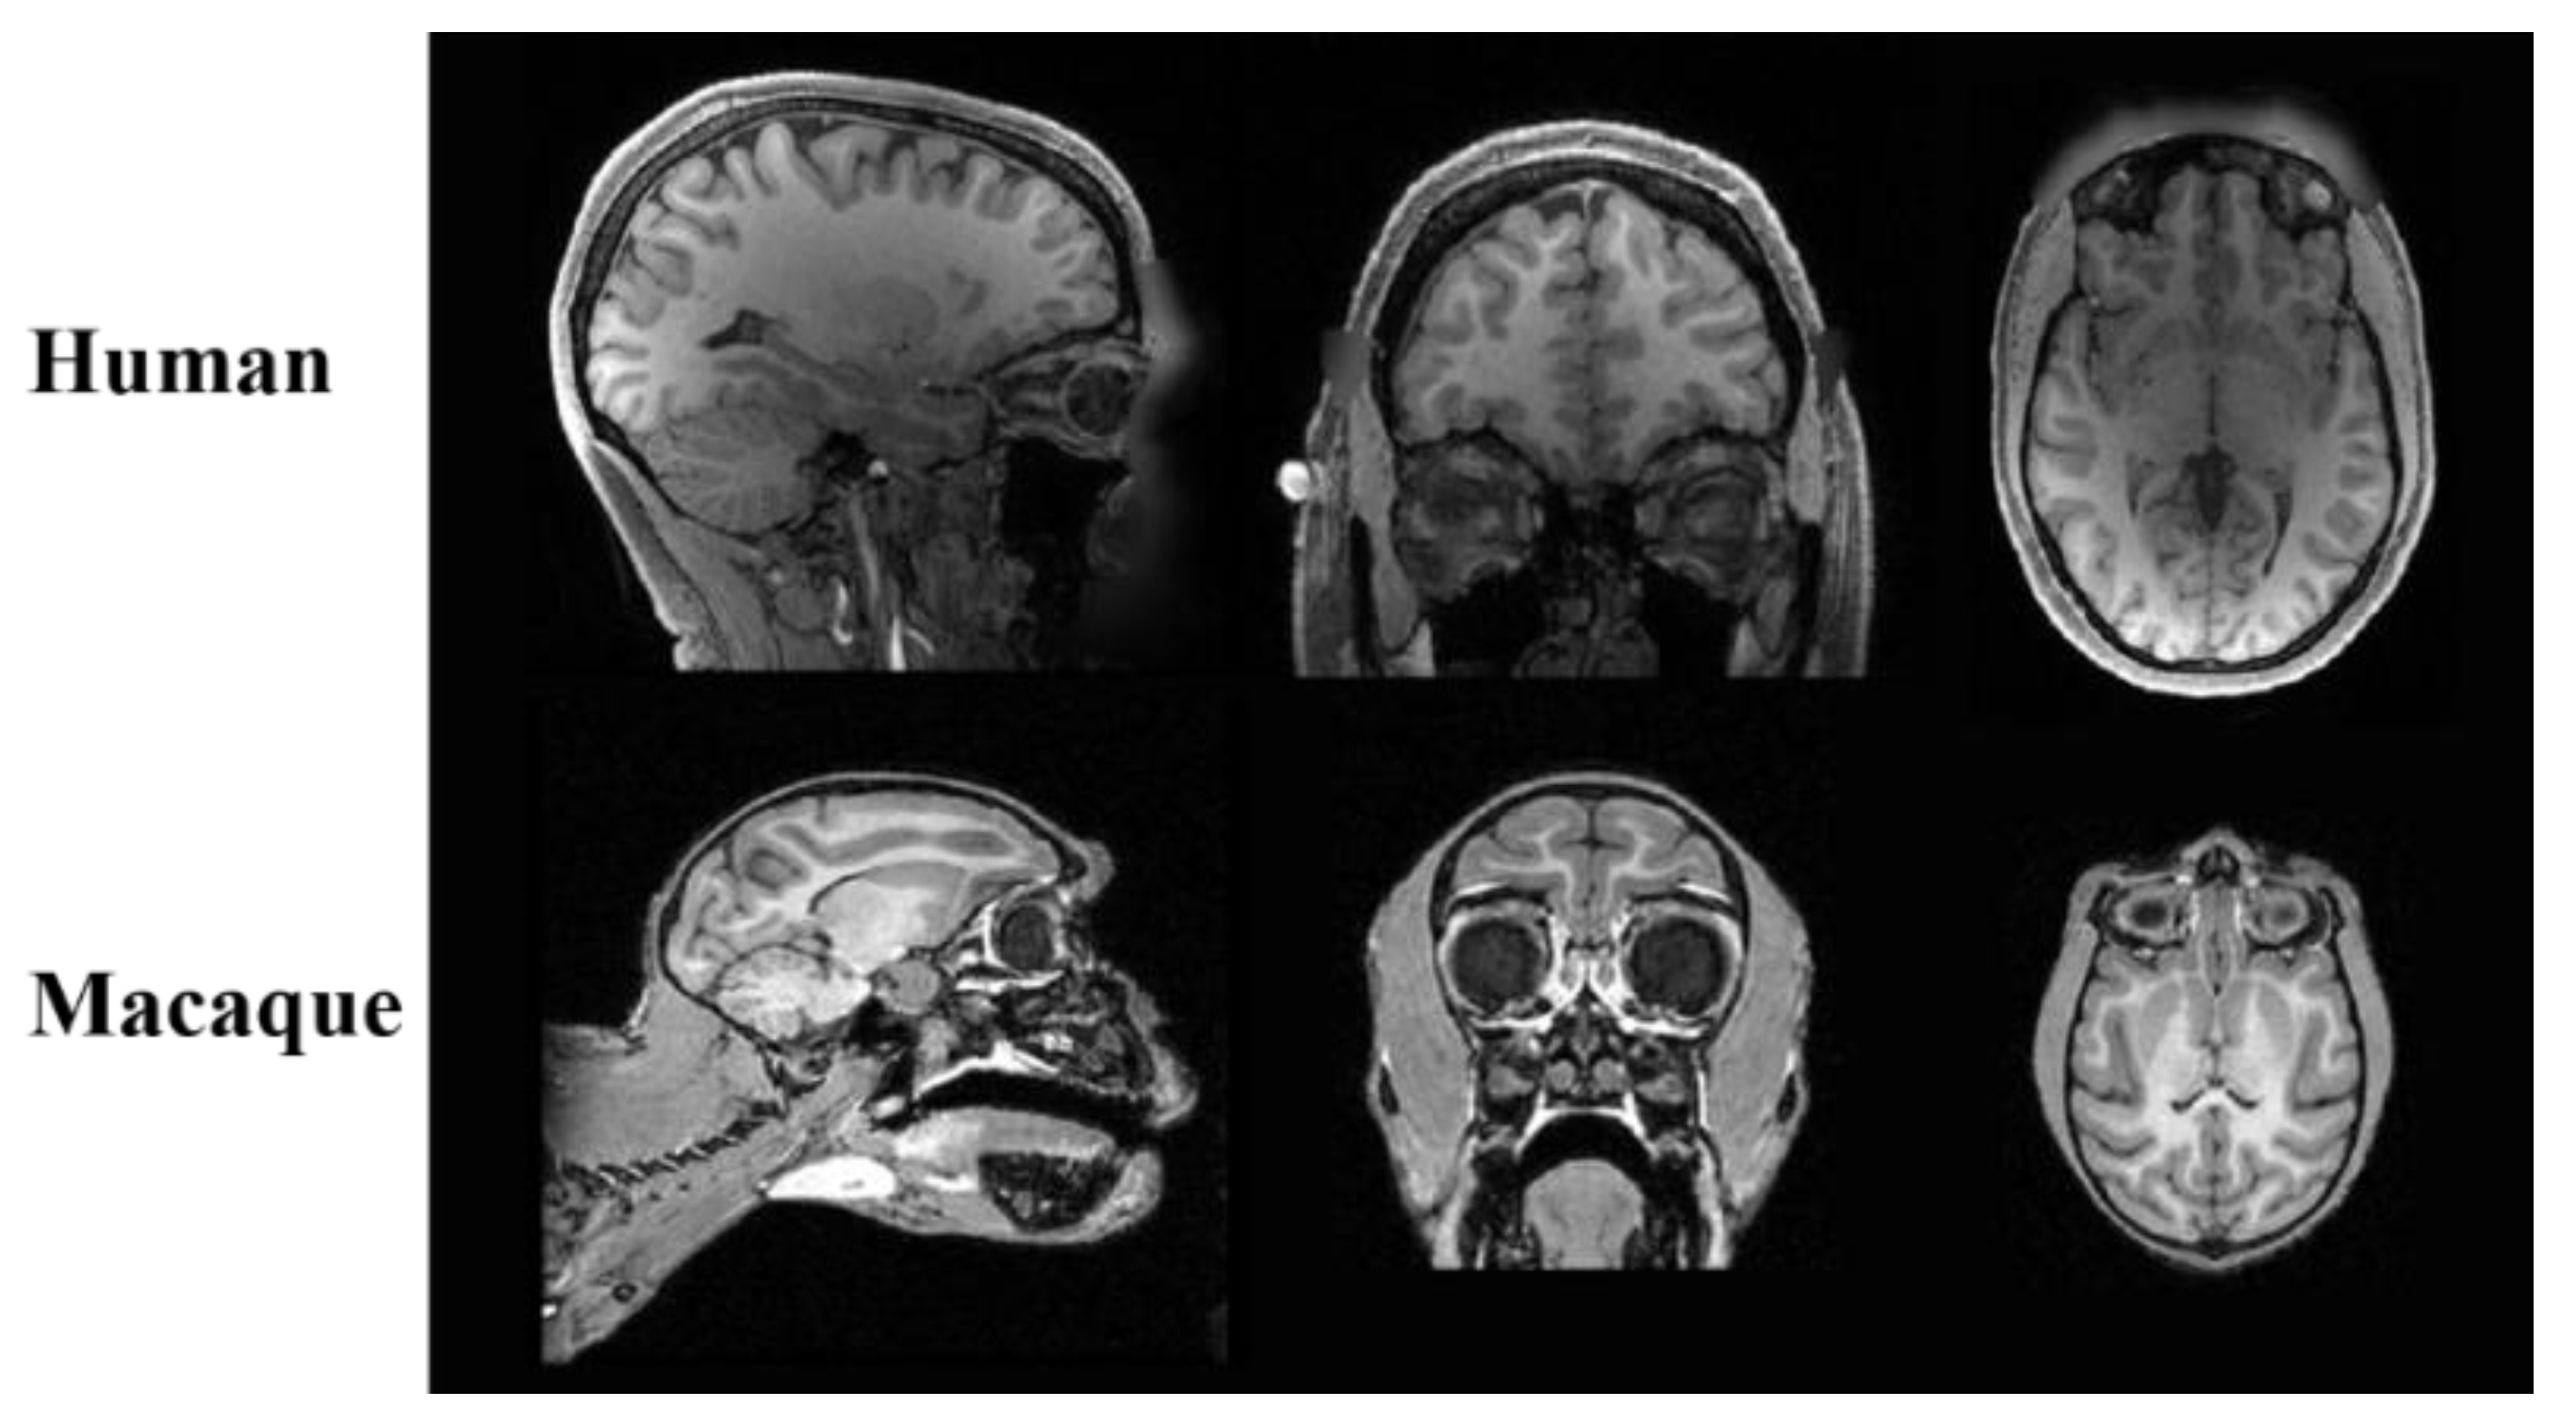

2.1. Dataset